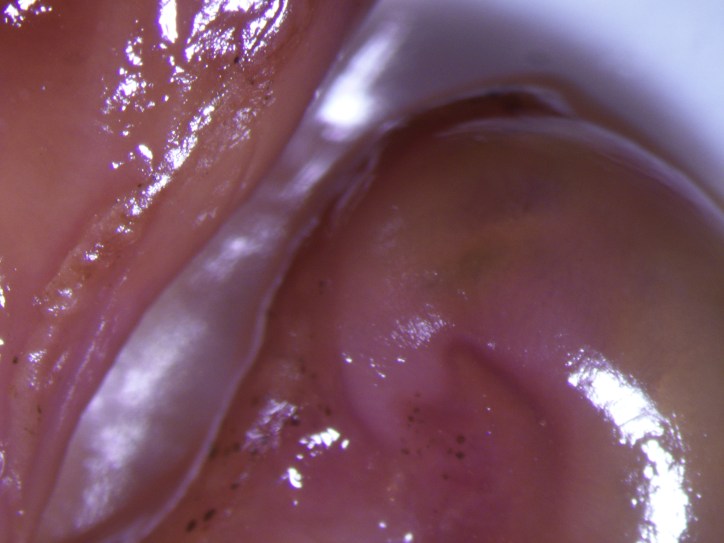

CSI10062 Publicerat den 6 mars, 2015 i MikroskåpbilderFull upplösning (2560 × 1920) ← Föregående Nästa →